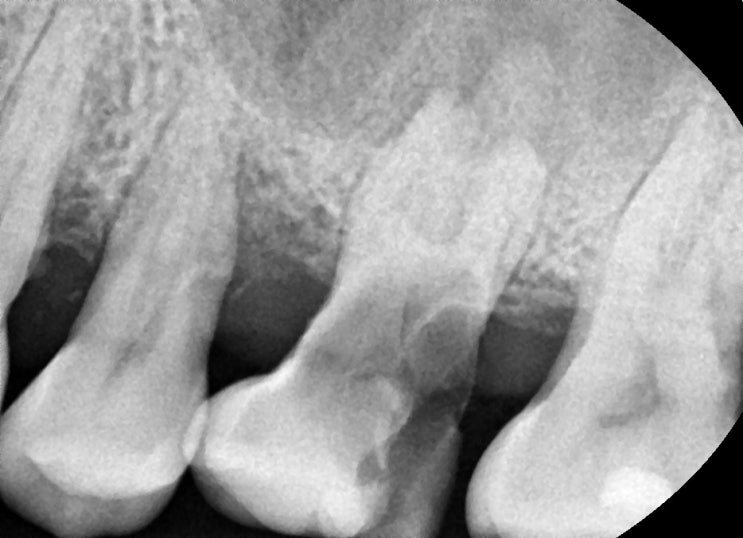

이런 치아는 신의 손 치과의사가 아니라 신이라도 못살립니다 하루 빨리 뽑으세요

건강보험에서 검진에 해당되는 수가가 워낙 저렴하다 보니 몇몇 환자분들은 치과치료비 견적 비교를 위해서...